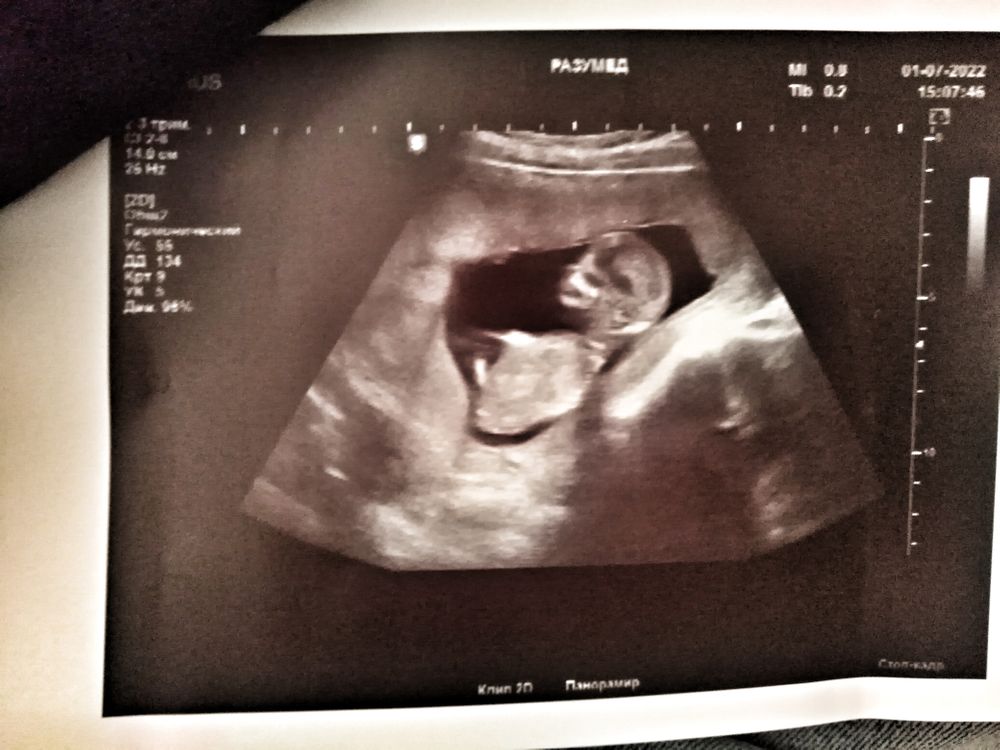

У меня на 1 скрининге сделали такое фото - со стороны попы и ножек малыша , так вот там прям капец что выросло )))), врач сказал вряд ли в девочку превратится уже 😀. А сбоку, как у вас, конечно ещё ничего не видно!

Cleo, у меня тоже очевидно было на первом скрининге, когда с попы посветили))))

Видимо так очевидны мальчики